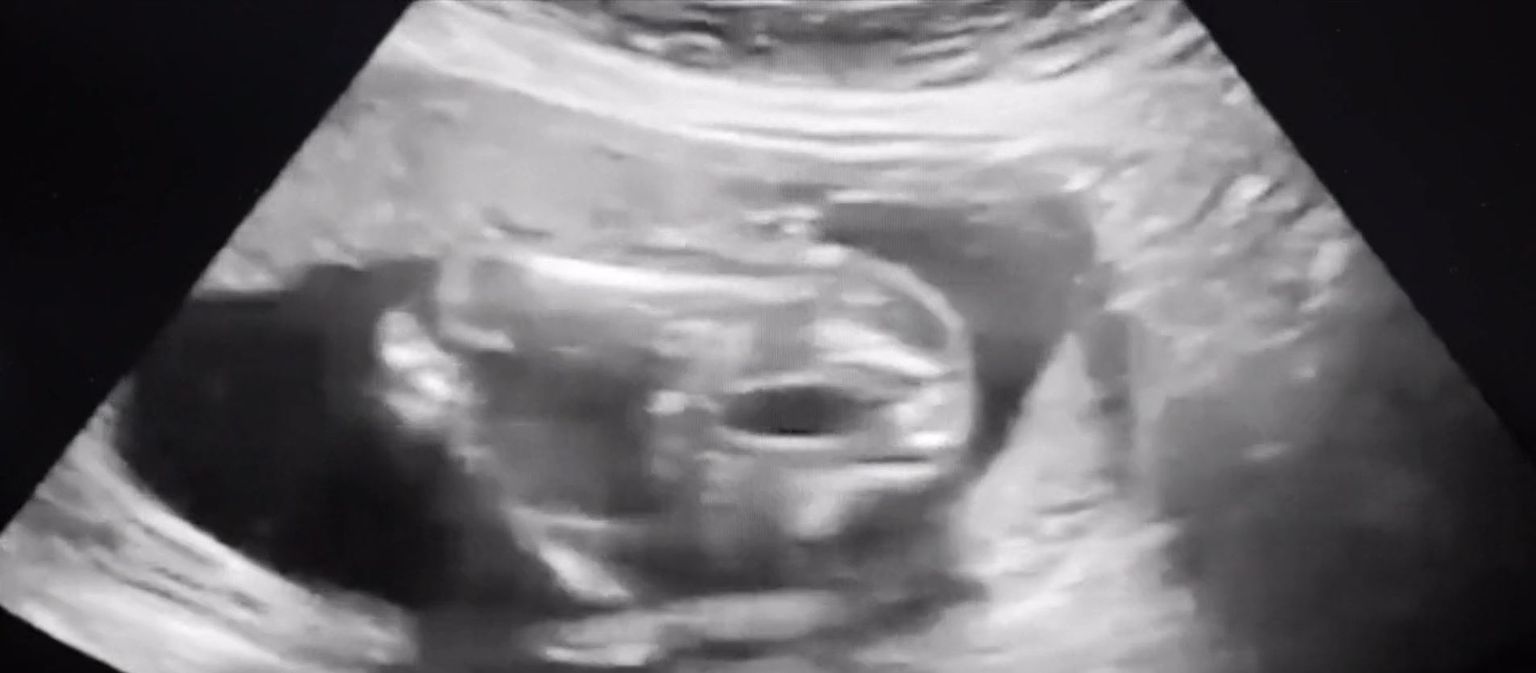

• Sve kasniji porodi - 5 Foto: DNEVNIK.hr

• Sve kasniji porodi - 4 Foto: DNEVNIK.hr

• Sve kasniji porodi - 3 Foto: DNEVNIK.hr

• Sve kasniji porodi - 2 Foto: DNEVNIK.hr

• Sve kasniji porodi - 1 Foto: DNEVNIK.hr